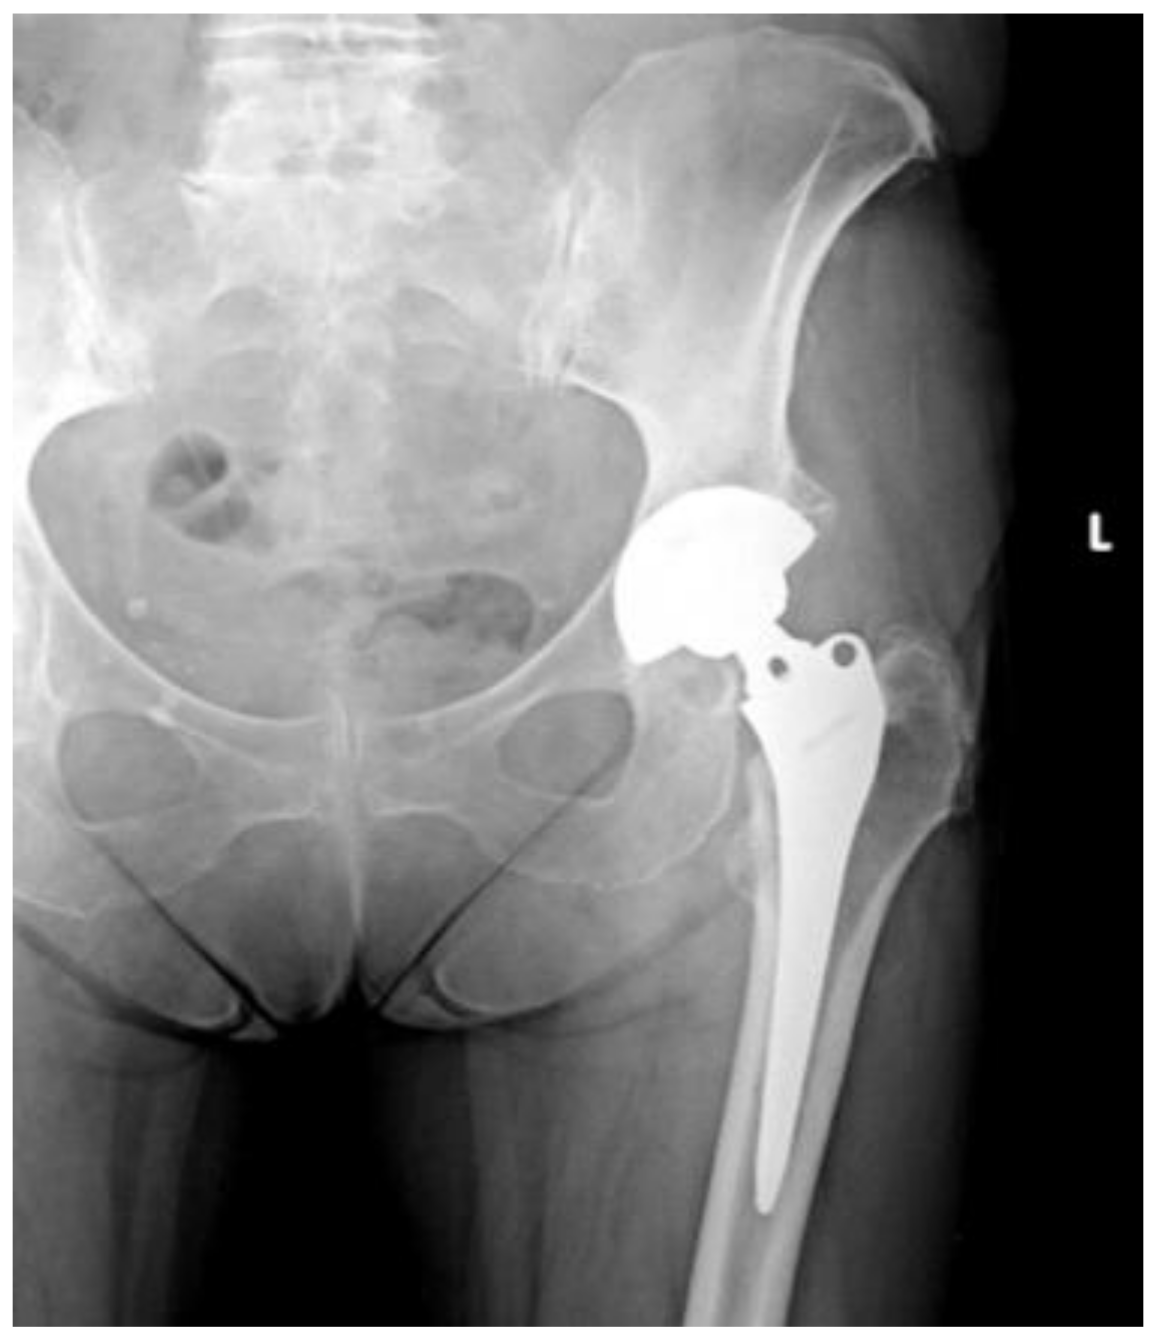

Of the 84 patients enrolled in this study, 44 patients (52.4%) received a THA with a straight stem (group A) (Figure 1 and Figure 2) and 40 patients (47.6%) received a THA with an anatomical stem (group B) (Figure 3 and Figure 4).

Figure 1.

Antero-posterior X-rays view of a total hip arthroplasty with straight stem (group A).